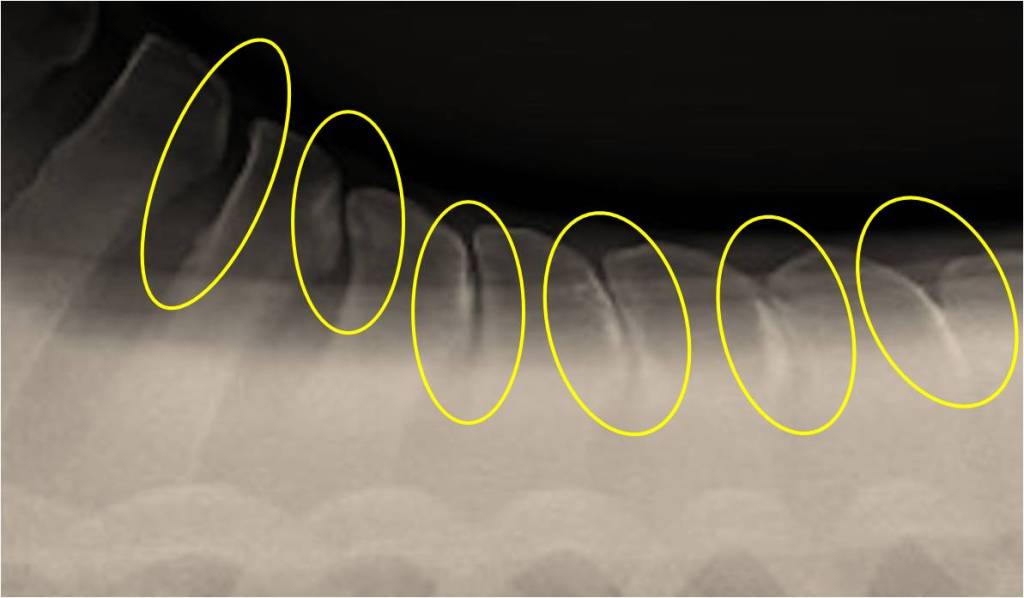

Prior to the 1980s we bought horses on flexion tests. Not much later, leg X-rays became the norm. What I have noticed in the past decade or so is that even youngsters these days may show early spinal issues that call for a full set of back and neck X-rays already in many a 3 yr. old even before being mounted.

However, X-ray pictures such as the above samples generally are more common in ridden horses. And, sadly, perhaps at least a partial result of paying less attention to rider education and seat.